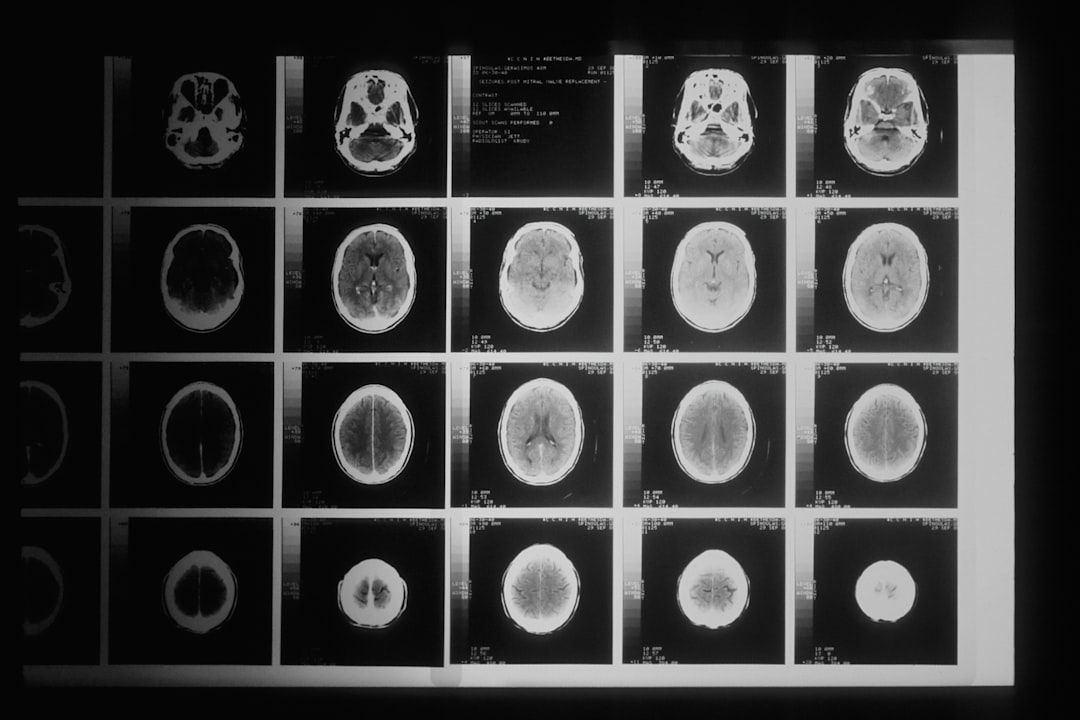

传统医疗AI主要停留在简单的图像识别阶段,比如在CT扫描中标记可疑结节。但2023年发布的腾讯觅影4.0系统已经能够实现多模态分析,同时处理影像、检验报告和电子病历文本。在一次临床试验中,该系统对早期肺癌的诊断准确率达到92.3%,甚至超过了部分资深放射科医生。

"AI不再是简单的工具,而是逐渐成为诊断团队的一员。"北京协和医院放射科主任金征宇教授这样描述当前的变化。他带领的团队与推想科技合作开发的肺炎AI诊断系统,在新冠疫情期间处理了超过50万份胸部CT,平均阅片时间从15分钟缩短到30秒。